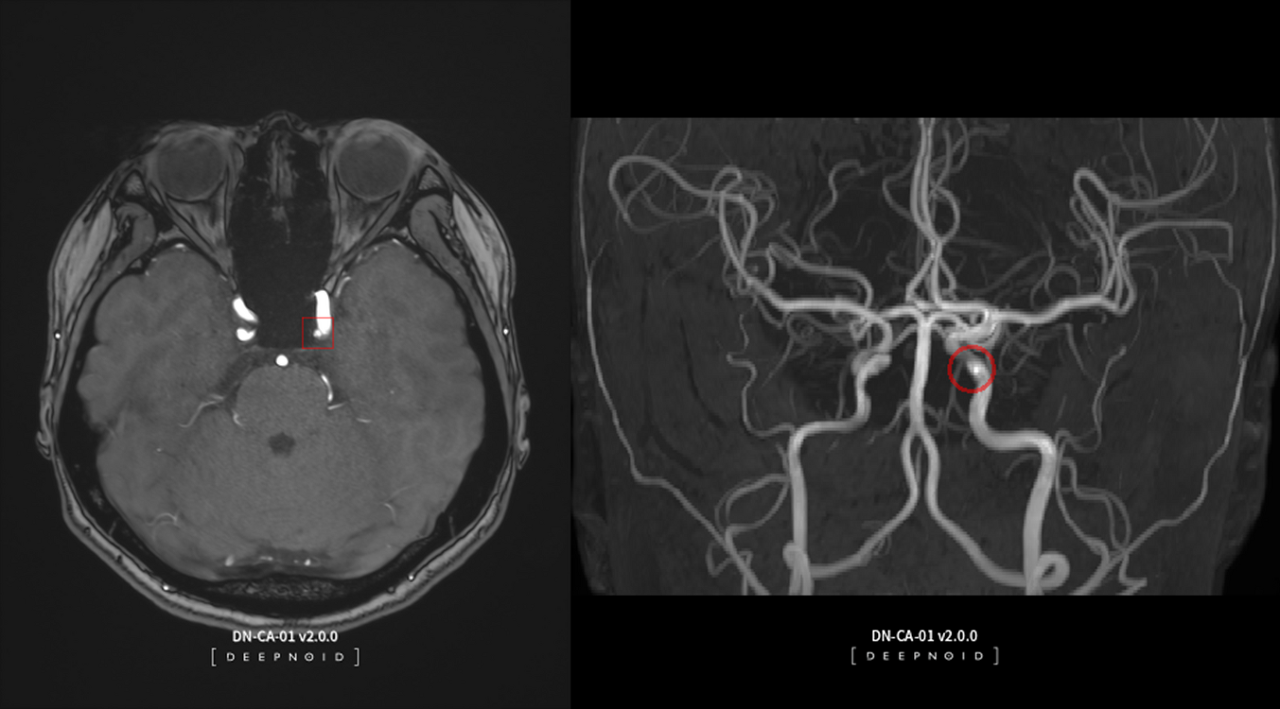

의료시장에서는 AI 기반 뇌동맥류 영상 진단 솔루션 딥뉴로(DEEP:NEURO) 혁신의료기술 선정과 고시 발령을 통해 매출 확대를 꾀한다.

올해 11월 1일부터 의료현장에서 딥뉴로를 비급여로 사용할 수 있게 됨에 따라 딥뉴로를 도입한 병원은 '뇌동맥류가 의심되는 환자'에게 해당 제품을 사용할 수 있게 된다.

딥뉴로로 인한 실질적인 매출은 비급여 시장 진출에 따른 행정절차 이후인 '24년 1분기부터 발생할 것으로 보인다. 현재 계약 기준 매출 추정치는 50억원이다.

AI 기반 뇌동맥류 영상 진단 솔루션 딥뉴로(DEEP:NEURO) 제품 사진.